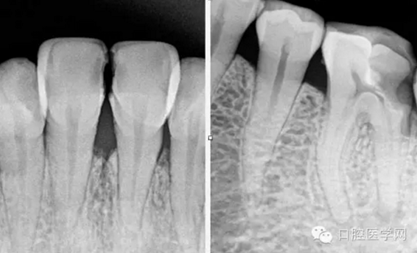

術(shù)前片(治療前知道齲壞的程度,根管的走向)

特殊情況可以插針拍片確定工作長(zhǎng)度(一般我比較相信根測(cè))

試尖(檢查是否恰填)

根充(從術(shù)后X光片可以看出根管充填完整,專業(yè)上叫恰充)